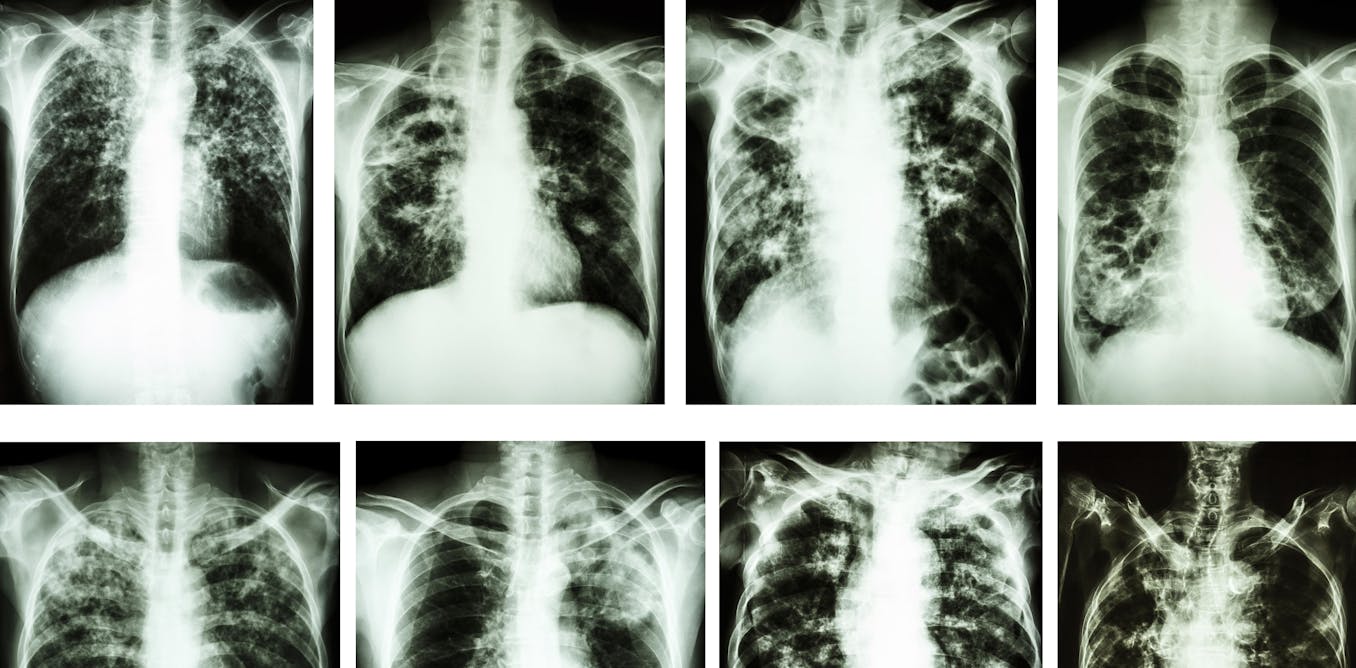

Открытая форма туберкулеза является одним из вариантов развития этого опасного заболевания. Фотографии наглядно показывают, как выглядят поражения легких и других органов при данной форме туберкулеза.

Фотографии открытой формы туберкулеза

Ниже представлены фотографии, на которых запечатлены характерные признаки открытой формы туберкулеза. Они помогут вам лучше понять и узнать о симптомах и стадиях данного заболевания.